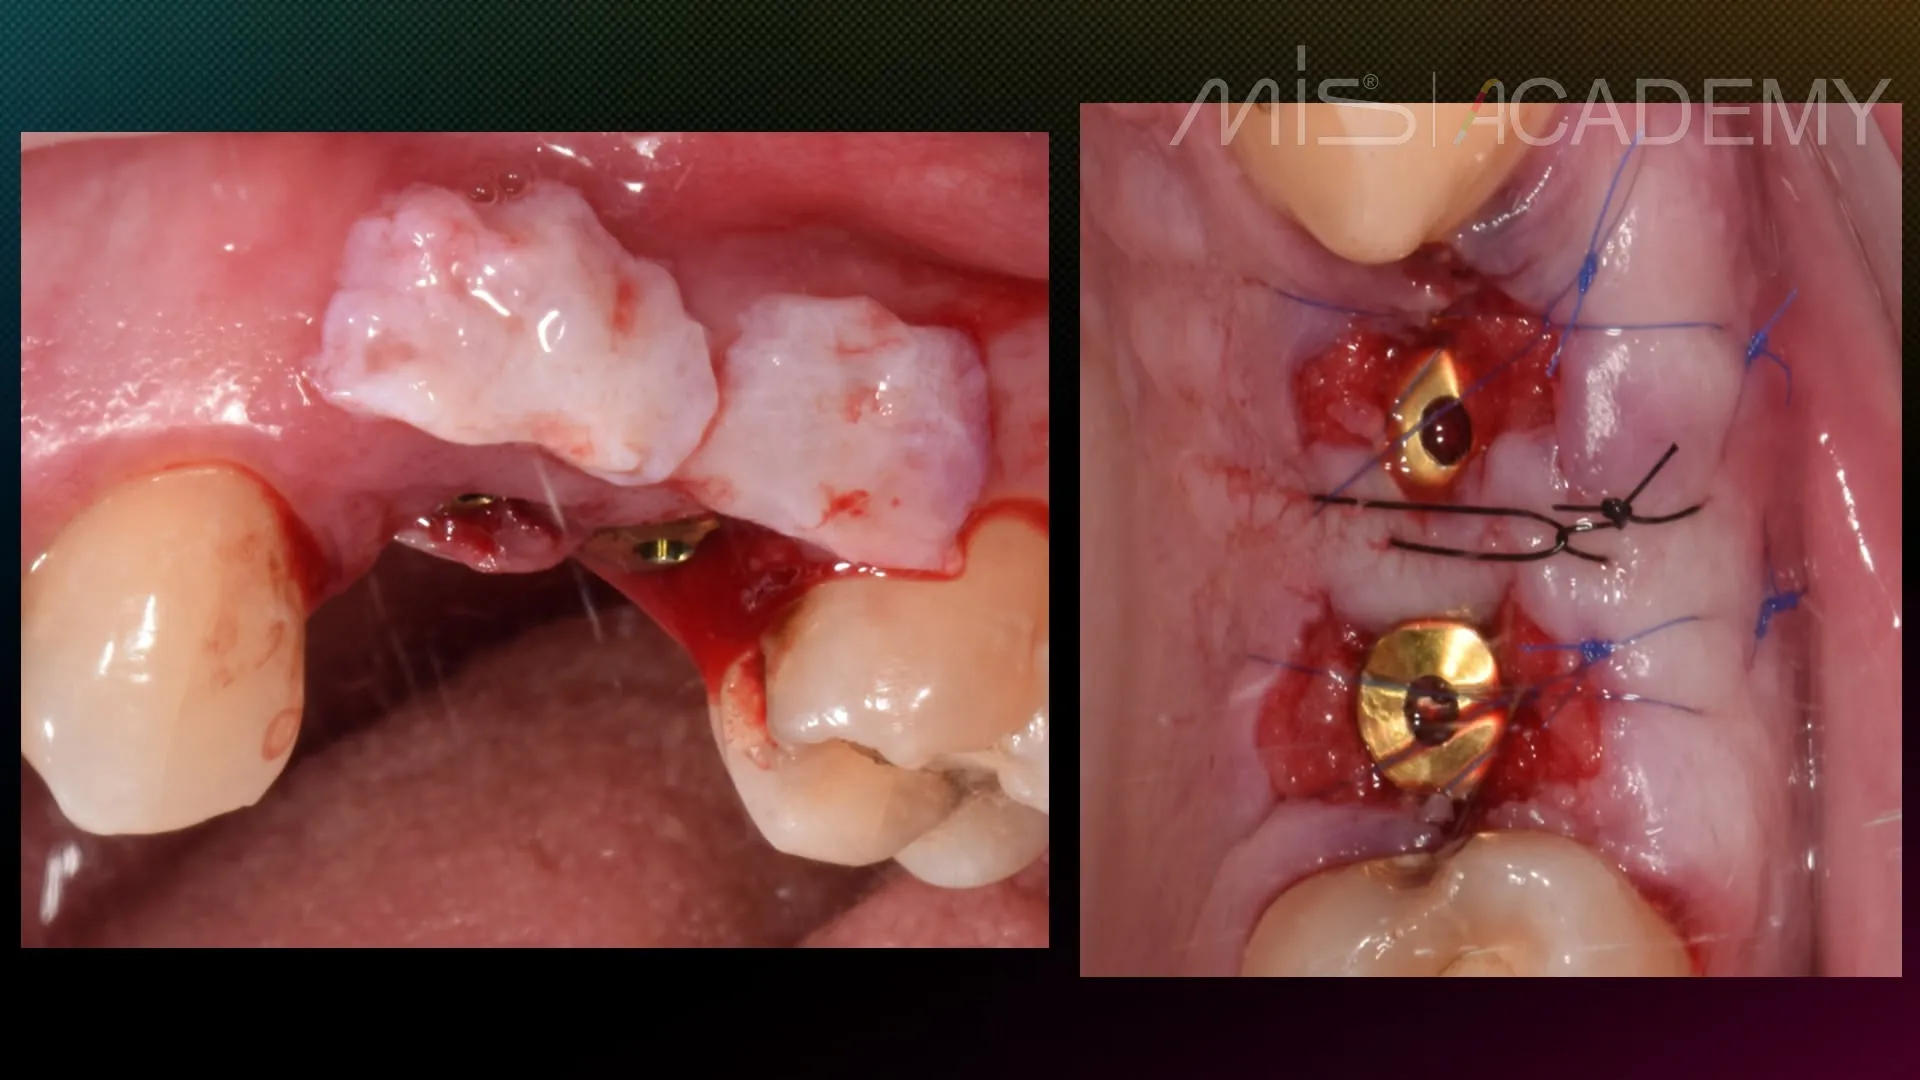

— Установка имплантатов MIS C1.

— CONNECT абатменты.

— Bio-oss, стимул-осс.